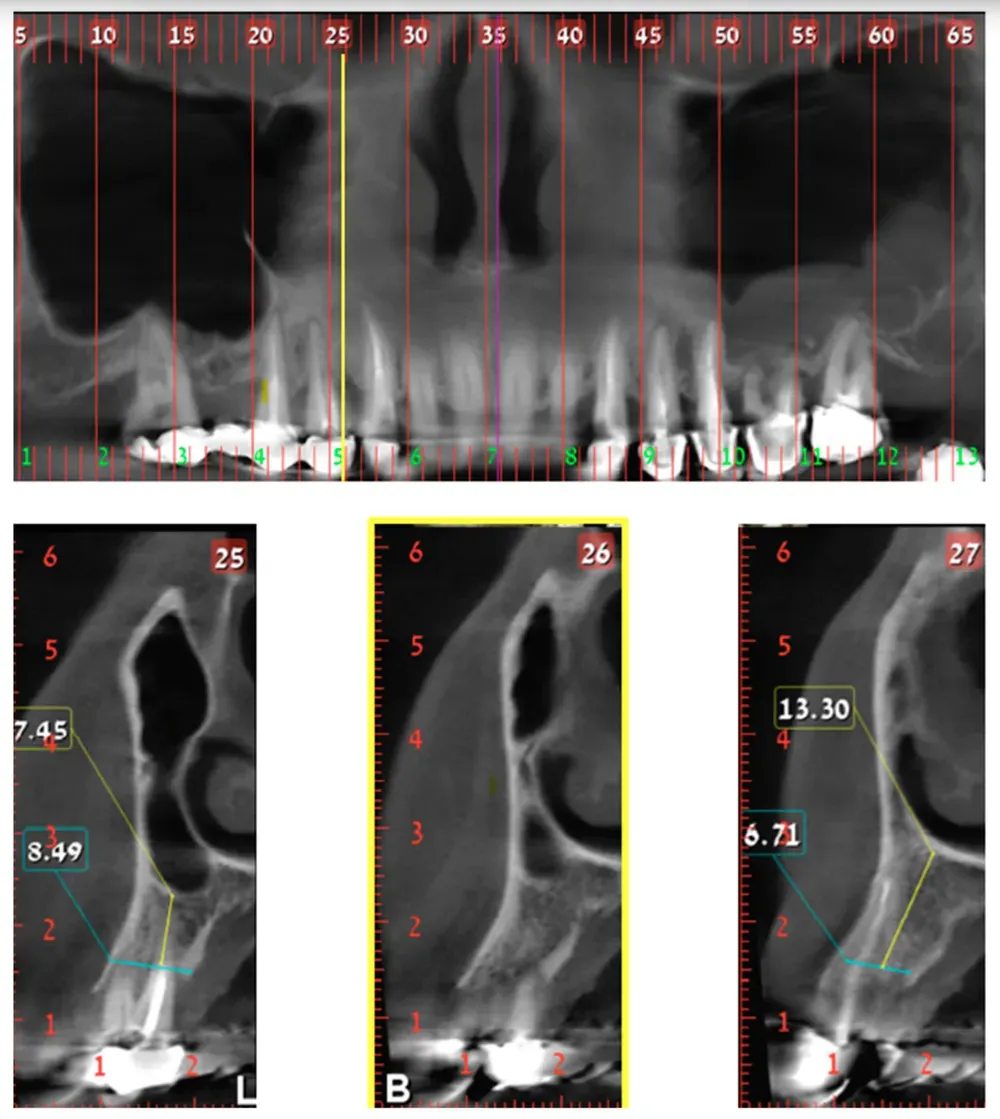

Nella Classe 1, il confine tra la cavità nasale e l’antro mascellare si trova sopra la parte distale del canino. In base ai dati raccolti in questo studio, si trova nel 17.2% dei casi.

Classe 1: la sezione numero 26, in giallo, delimita il confine distale della cavità nasale e si trova sopra la parte distale del canino. Da Yahya et al. (2021). Licenza CC4.0.

La Classe 2, dove il confine naso-sinusale si trova tra il margine distale del canino e quello del secondo premolare, appare nel 66% dei casi esaminati. La Classe 3, con il confine distale al margine mesiale del primo molare, si manifesta nel 16,8% dei pazienti.